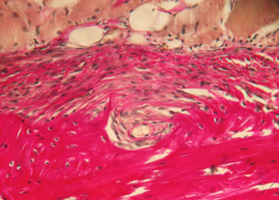

В норме кость нижней челюсти кролика имеет губчатое строение и представлена как компактным пластинчатым, так и губчатым балочным компонентами.

Пластинчатый компонент располагается по периферии на поверхности кости и представлен кортикальной пластиной, имеющей остеонный тип строения.

Губчатый компонент, имеющий трабекулярно-балочное строение, расположен внутри под кортикальной пластиной и представлен балками губчатой костной ткани, пространство между которыми заполнено миелоидной тканью, содержащей клетки красного костного мозга, единичными жировыми клетками и сосудами микроциркуляторного русла — капиллярами (рис. 1).

Губчатый компонент, имеющий трабекулярно-балочное строение, расположен внутри под кортикальной пластиной и представлен балками губчатой костной ткани, пространства между которыми заполнены миелоидной тканью, содержащей клетки красного костного мозга, единичными жировыми клетками и сосудами микроциркуляторного русла – капиллярами (рис. 1).

Рис. 1. Строение нижней челюсти кролика в норме. Черными стрелками указан компактный компонент, синими – губчатый.

Между балками губчатого вещества видна миелоидная ткань, клетки жировой ткани и капилляры (указаны зелеными стрелками).

Окраска – пикрофуксин по ван Гизон, х100.